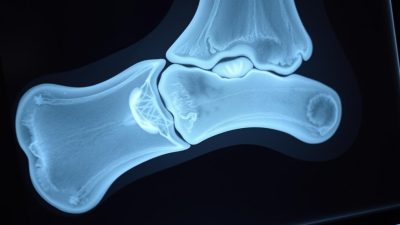

Pencitraan yang Digunakan

Teknik pencitraan medis memainkan peran penting dalam diagnosa Avascular Necrosis. Beberapa metode pencitraan yang umum digunakan meliputi:

- Rontgen untuk melihat perubahan pada struktur tulang

- MRI untuk mendeteksi perubahan awal pada tulang dan jaringan lunak

- CT Scan untuk memberikan gambaran detail tentang struktur tulang

- Bone Scan untuk mendeteksi area dengan peningkatan aktivitas metabolisme tulang